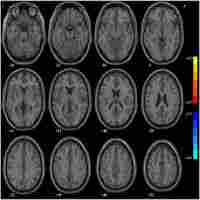

| Abstract | Background Although symptoms of depressive episodes in patients with bipolar depressive episodes (BDE) and major depressive disorder (MDD) are similar, the treatment strategies for these disorders are completely different, suggesting that BDE and MDD have different neurobiological backgrounds. In this study, we examined the relationship between brain function and clinical symptoms, particularly cognitive function, in female individuals with bipolar disorder and MDD experiencing depressive episodes. Methods Regional homogeneity (ReHo) was analyzed in 51 medication-free female patients with BDE, 63 medication-free female patients with MDD, and 45 female healthy controls (HCs). Depressive symptom severity was assessed using the 24-item Hamilton Depression Rating Scale (HAMD-24), and multidimensional cognitive function was evaluated using the MATRICS Consensus Cognition Battery. Partial correlation analysis was used to explore the links between the brain regions and clinical characteristics. A support vector machine (SVM) was used to assess the classification accuracy. Results Compared with HCs, patients with BDE and MDD had decreased ReHo in the left lobule VI of the cerebellum and increased ReHo in the left precuneus. Patients with BDE also had reduced ReHo in the left lobules IV–V of the cerebellum and increased ReHo in the right putamen, unlike patients with MDD who had no significant differences in these regions. Patients with BDE exhibited more severe cognitive deficits in processing speed, attention, word learning, and overall cognitive function than those with MDD. In patients with BDE, a significant negative correlation was found between the right putamen and HAMD-24 scores. However, no significant association was observed between abnormal ReHo levels and cognitive function. The SVM effectively differentiated between patients with BDE, MDD, and HCs. Conclusion Cognitive impairment was more severe in female patients with BDE than in those with MDD. Changes in the ReHo values of the right putamen and left lobules IV–V may serve as unique neuroimaging markers for BDE. Alterations in the ReHo values of the left precuneus and left lobule VI could serve as common pathophysiological mechanisms for BDE and MDD in women and indicate depressive states. |